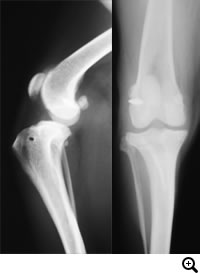

膝蓋骨脱臼グレード2〜3

膝蓋骨脱臼グレード2〜3とは

膝蓋骨が大腿骨遠位にある滑車溝から内方もしくは外方に脱臼する疾患です。膝蓋骨外方脱臼の症例では、内方脱臼よりも強い症状を呈することが多いです。

グレード2とは、膝蓋骨を指で押すと簡単に脱臼しますが、指を離しても自然には元に戻らない状態です。日常生活の中で自然に脱臼することがあり、元に戻ると跛行がおさまります。

グレード3とは、普段から膝蓋骨が脱臼したままで、指で押すと正常な位置に戻りますが、指を離すと脱臼した位置にもどる状態です。

若い時期にみられた場合は放置しておくとグレード4にいたる可能性があること、何らかの症状があり日常生活の中で脱臼している場合は膝蓋骨内側の軟骨がすり減り、痛みが強くなるなどの理由から手術による整復を必要とします。

診断

触診、レントゲン検査

外科手術。おもに、Block Resectionという関節軟骨を温存したまま膝蓋骨がおさまっている溝を深くする方法と、脛骨粗面転移術といい内側に変位している膝蓋靭帯の付着部である脛骨粗面の位置を正しい位置にもどす方法とを組み合わせて行います。

前十字靭帯断裂とは

膝関節の安定化を担っている前十字靱帯が断裂することにより、膝関節の不安定性が発現します。断裂した前十字靱帯の断端から炎症性のメディエーターが放出されるため、関節炎が起こります。

触診、レントゲン検査、関節鏡検査

関節外制動法(Lateral Suture Stabilization)など。前十字靭帯と同様の働きをする位置に合成靭帯を設置し、膝関節を安定化させる手術法。